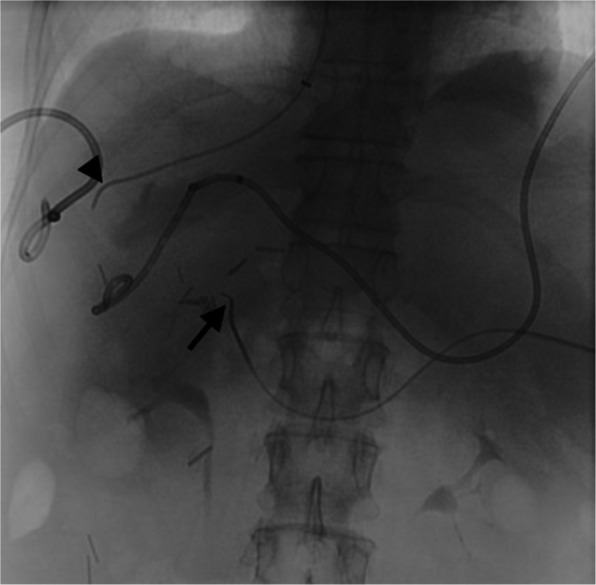

腹腔镜胆囊切除术治疗急性胆囊炎是最常用的手术之一,通常被认为是一种安全的手术,并发症风险低。血管和胆道损伤很少见,但后果严重。目前还没有进行系统的研究来描述这些情况下的最佳治疗策略,这些策略通常是根据具体情况进行管理的。本报告描述了一例患者行腹腔镜胆囊切除术,并发胆总管和门静脉主干结扎,导致肝梗死、肝周脓肿、门静脉高压合并腹水和门脉性充血性肠病。本病例的重点是处理该患者的血管损伤,并成功地通过经脾和右颈内静脉进入血管内门静脉重建。

Laparoscopic cholecystectomy for acute cholecystitis is one of the most performed surgeries and is generally regarded as a safe procedure with a low risk of complications. Vascular and biliary injuries are rare but have severe consequences. No systematic studies have been performed to delineate optimal treatment strategies in these scenarios, which are typically managed on a case-by-case basis. The present report describes a patient who underwent a laparoscopic cholecystectomy, complicated by common bile duct and main portal vein ligation, resulting in hepatic infarcts, perihepatic abscess, and portal hypertension with ascites and portomesenteric congestive enteropathy. This case focuses on management of this patient's vascular injury, which was successfully treated by endovascular portal venous reconstruction using trans-splenic and right internal jugular vein access.